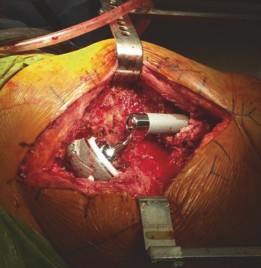

Explantation:

The existing acetabular component, any cement mantle, and osteolytic membrane or fibrous tissue are meticulously removed. Use of specialized explantation tools, osteotomes, and a high-speed burr may be necessary. Ensure all foreign material is removed, leaving a clean, bleeding bone bed.

- This image might depict a large acetabular defect after explantation, highlighting the extent of bone loss.

Acetabular Preparation & Bone Grafting

- Defect Assessment and Debridement: Following explantation, the extent of the acetabular bone loss is meticulously assessed and correlated with pre-operative imaging. All remaining fibrous tissue, cement, and sclerotic bone are debrided to expose healthy, bleeding host bone.